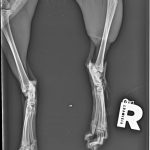

A sokktalanítás után, bódításban tudták csak megvizsgálni, borzasztóan félt és hatalmas fájdalmai voltak. Sajnos a fájdalom oka a hátsó lába iszonyatos sérülése volt. A térde szilánkosra törve és a lágy részek rendkívül súlyosan roncsolódtak. Az első orvosi vélemények szerint 75% az esélye, hogy ezt a lábat nem tudják megmenteni már, tegnap este azután az ortopéd orvos is megvizsgálta és az ő véleménye szerint sem menthető a lábikó. A mai nap stabilizálták az állapotát, erősítik kicsit és holnap sor kerül a műtétre. Az első lábacskája szintén zúzódott, nagyon be van dagadva, itt azonban megvan a remény a teljes gyógyulásra.